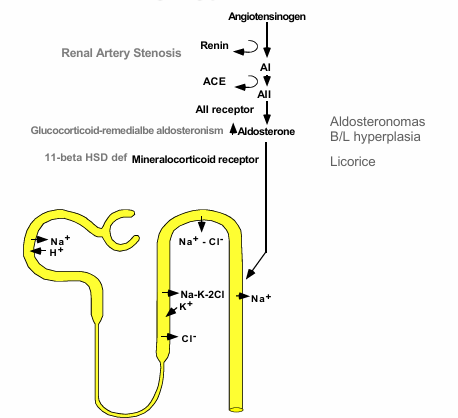

glucocorticoid remediable aldosteronism

normal v. AME for lumen to blood

normal v. AME with licorice ingestion for lumen to blood

primary aldosteronism

pathogenesis of many acquired or genetic forms of secondary hypertension

tubules with thiazide and loop diuretics